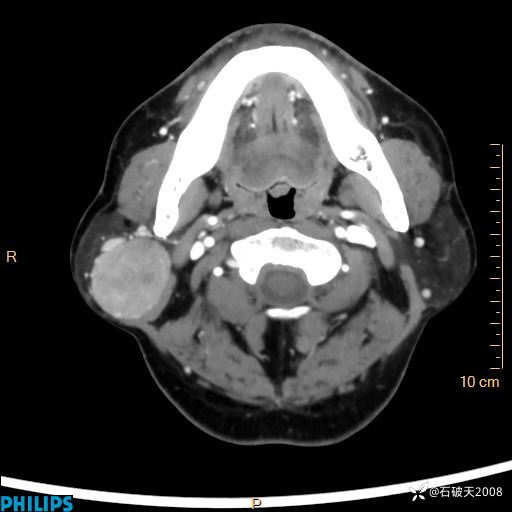

病例分享:颈部占位,一周后公布病理

男 57岁 主 诉:发现右侧颌下肿物1月余。

现病史:1月余前家属发现右侧颌下肿物。局部皮肤无红肿、热痛,无吞咽困难,无异物感,无恶心、呕吐,无头痛、头晕,无胸闷、胸痛,无发热、咳嗽、咳痰及呼吸困难。于我院行体表肿块彩超检查(2024.03.15我院)示:右侧耳下皮下软组织内低回声,未治疗。今为进一步治疗门诊以“腮腺肿瘤”为诊断收住我科,发病来患者神志清,精神可,饮食、睡眠及大小便正常,体重无明显下降。

平扫